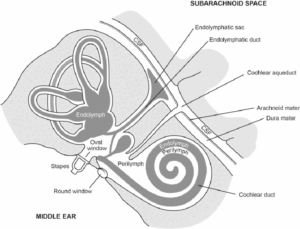

回転性めまい(vertigo)、眩暈(dizziness)、平衡感覚異常を経験する多くの人々が、耳閉感、聴覚過敏、聴力低下、耳鳴りのような耳症状を伴っています。

頭蓋内圧や脳圧の亢進、または頭蓋内高血圧の症状をお持ちの方が頻繁に来院されています。目の奥から頭痛が発生したり、心臓の鼓動に合わせて聞こえる拍動性耳鳴りがあったり、悪心、嘔吐、めまいを訴えられます。一晩中横になっている姿勢では脳浮腫がさらに悪化する可能性があるため、朝起きる時に頭痛があり、咳をする時や頭を下げる時のように頭蓋内圧を増加させる行為によって頭痛がさらに悪化するともおっしゃいます。また、首、肩、背中部位の痛みが多く、視神経浮腫による羞明や目のかすみといった眼症状を伴い、耳鳴り、ジストニア、斜頸、後頸部痛などの症状を訴えられます。